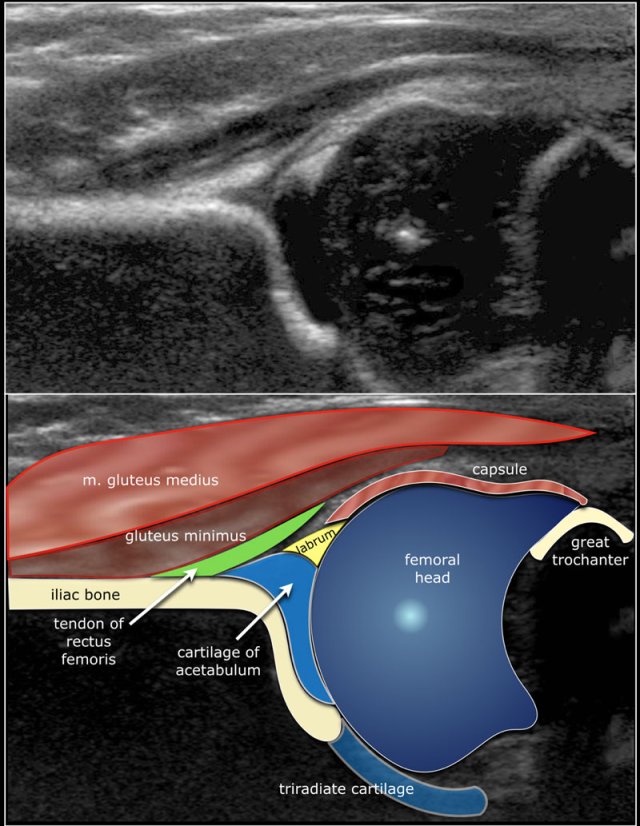

As a consequence the Graf classification of hip dysplasia is mainly based on the morphology of the iliac bone, where we look at the shape of the acetabulum, the bony and cartilaginous acetabular rim, labrum and position of the femoral head.

Since ultrasound has the advantage of also displaying the cartilagenous structures, we can also look at the coverage of the femoral head by the cartilage of the acetabulum and the labrum.

Here the anatomy in the coronal plane.

First three points of interest need to be indentified in the image:

1. Centre of labrum

2. Lower limb of the iliac bone (=Undersurface of the medial border of the acetabulum where the iliac bone meets the triradiate cartilage)

3. Bony rim of acetabulum. When the bony rim is angular this point is easily recognized. When rounded this point is defined as the point where the concavity of the bony acetabular roof changes into the convexity of the ilium